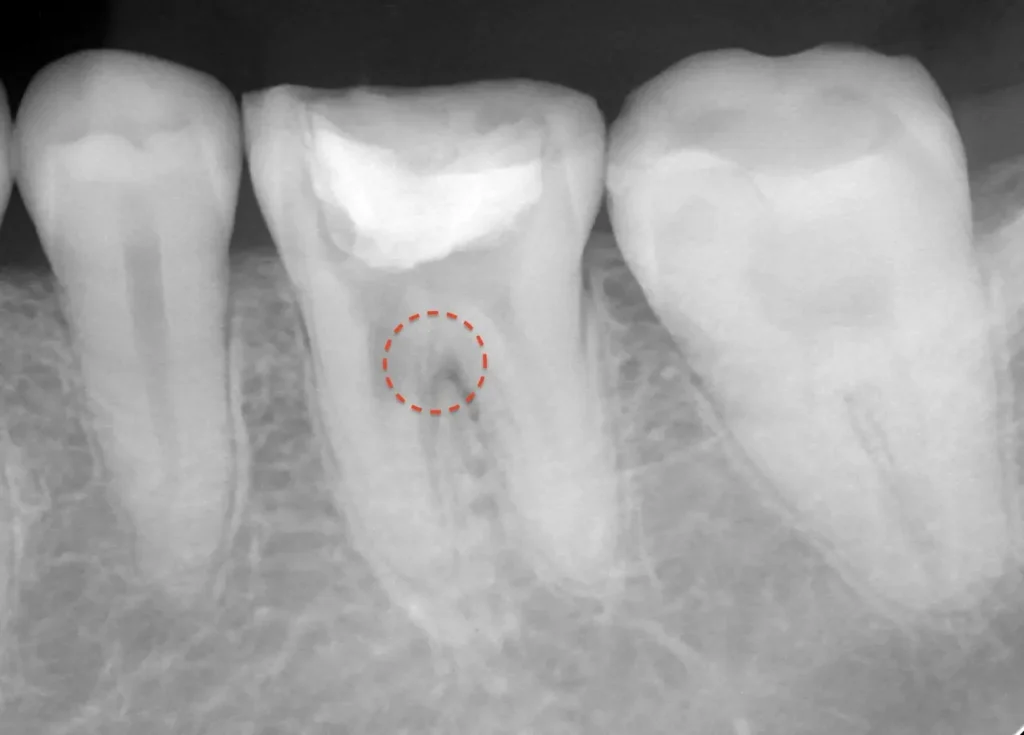

自費根管治療症例2 治療前

左下の奥歯が根の治療を受けているが治らない。

初診時

管の分かれている部分に根の治療による穿孔がありました